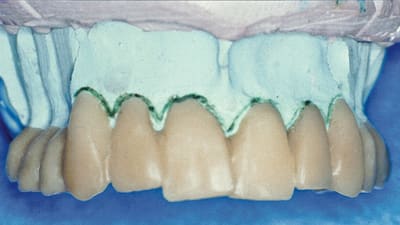

Online Only Online Only Different Esthetic Techniques Used in Combination to Recover the Smile By Daniel Sundfeld Neto, Diego Sucena Pita, DDS, Renato Herman Sundfeld, DDS, Ricardo Coelho Okida, DDS, Rodrigo Sversut de Alexandre, DDS, Vanessa Rahal, DDS August 01, 2010 10 min read